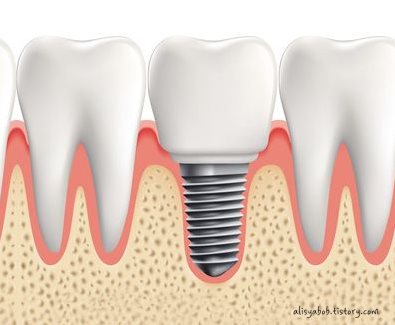

임플란트는 치아가 빠진 부위에 치워 버리리 역할을 하는 인공 치근을 고정하고 그 위에 지대 주를 연결한 이후에 보철물을 올려 마치 자연치아 위 기술을 하는 인공 치아 시립 치료 형태를 말합니다. 임플란트 치료 과정은 진단 1차/2차 수술 보철물 장착 수술 후 관리 등을 거치게 되는데요,